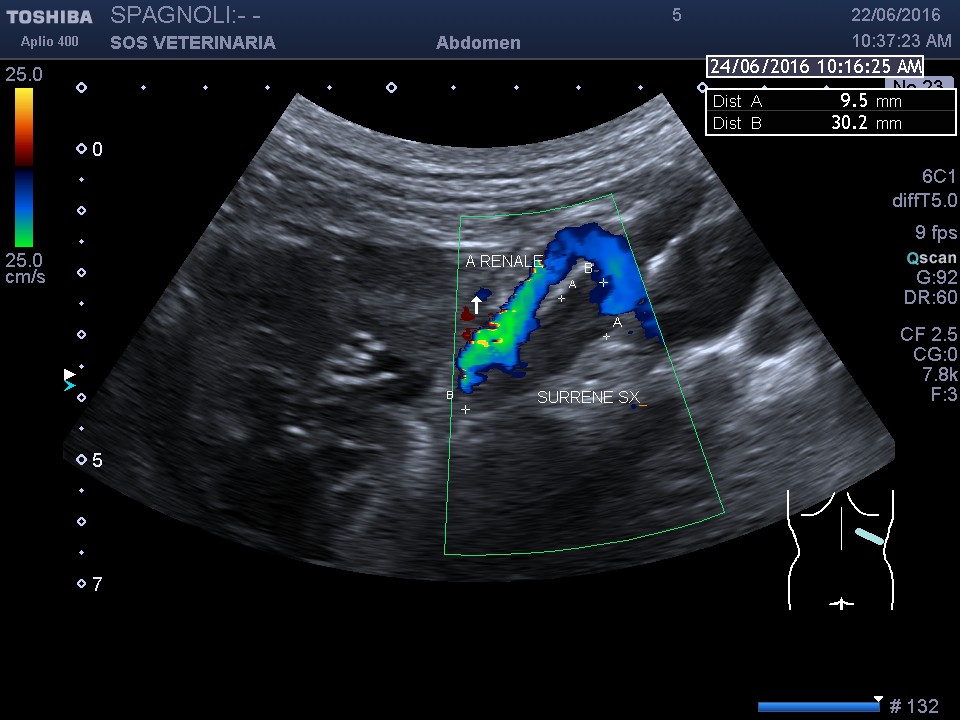

esame ecografico

evidente iperplasia della surrene sx le surrenali delle razze giganti sono molto piu’ difficili da visualizzare (sonda utilizzata da 6,5 mHz) e di dimensioni inferiori alle razze toy in proporzioni alla massa corporea,il limite di riferimento e’ impossibile stabilirlo per tutte le razze ci si affida al valore massimo di 7, 5 mm ai poli

nella destra asse lungo i valori superano di poco il riferimento

anche in asse corto si supera il valore di riferimento